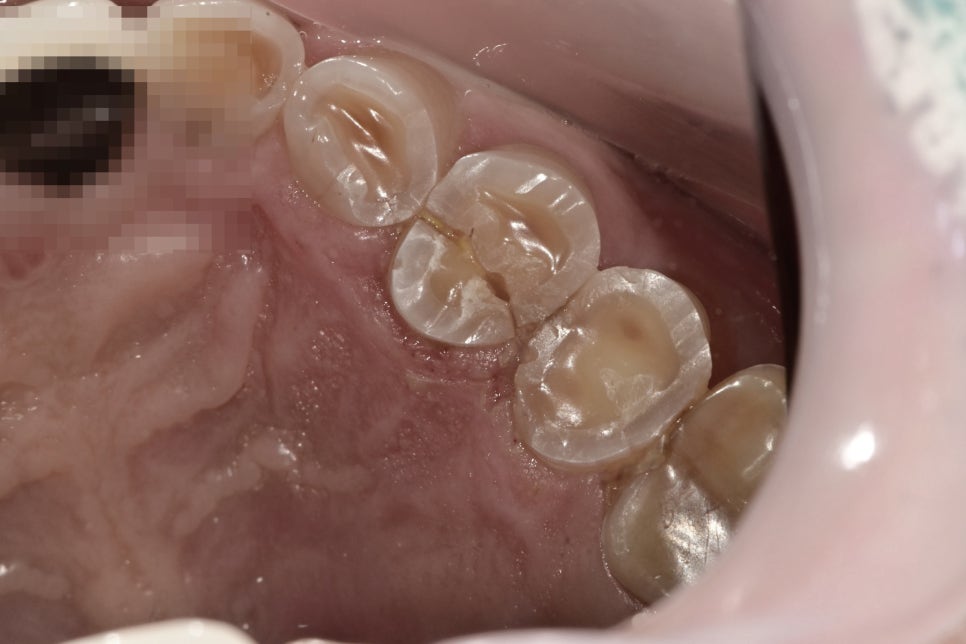

가로로 파절선이 관찰된 파절된 치아

중장년층의 환자분으로 턱 근육이 발달되어 있으시고 평소 딱딱하고 질긴 음식을 즐겨드시는 습관이 있으시기 때문에

해당 치아뿐만 아니라 전반적으로 치아가 마모가 되어있고, 전반적으로 실금들을 관찰할 수 있었습니다.